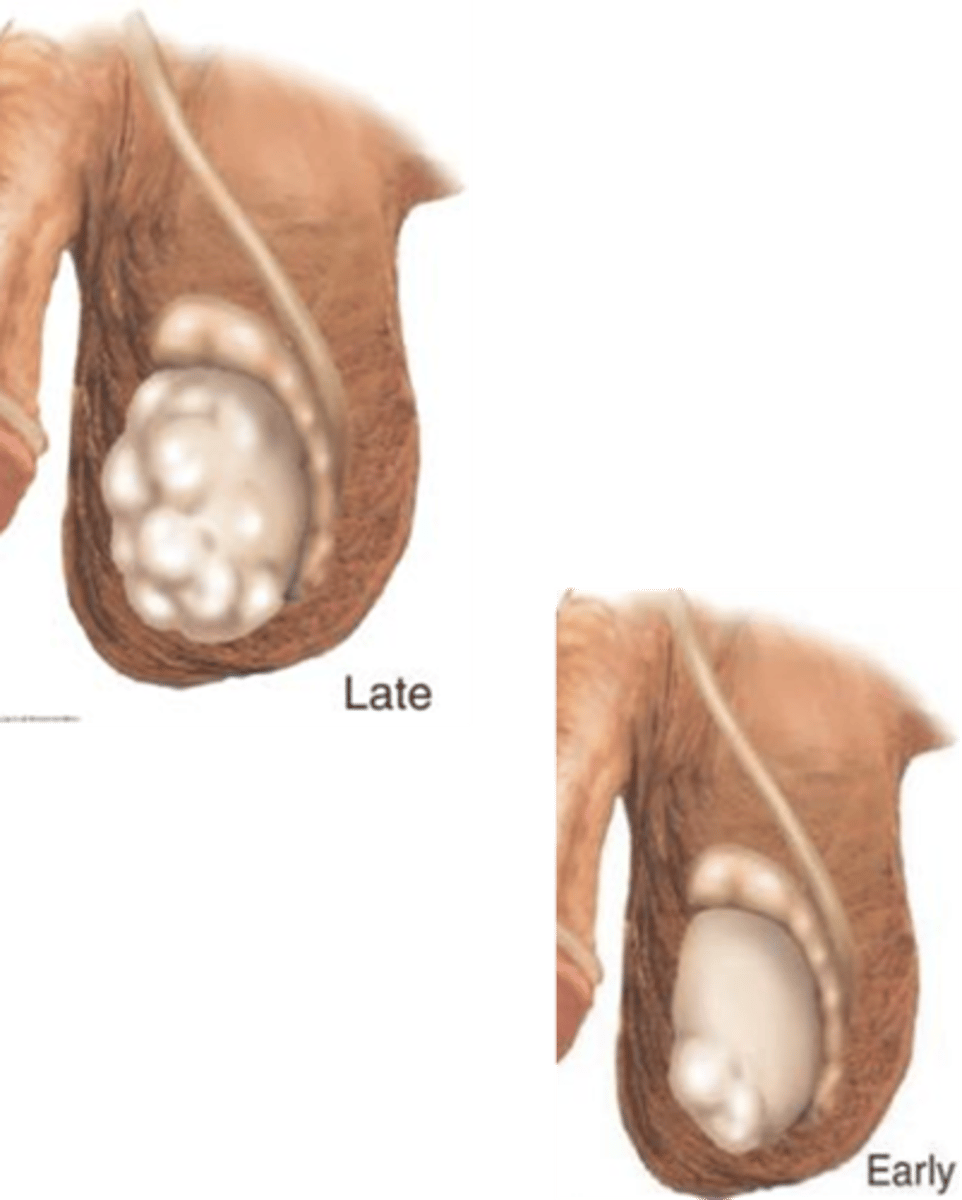

What age range does testicular cancer tend to affect? What is a big risk factor for this pathology?

Young men age 20-35; cryptorchidism

What are some s/sxs of testicular cancer?

Unilateral nodule, painless testicular enlargement (any firm large area is suspicious, CA is the diagnosis until proven otherwise), ache or heavy sensation, secondary hydrocele, +/- pain, possibly asymptomatic, gynecomastia

What is the role of scrotal ultrasound in diagnosing testicular cancer?

Seen as an extension of the PE, can differentiate intrinsic vs. extrinsic & solid vs. cystic masses